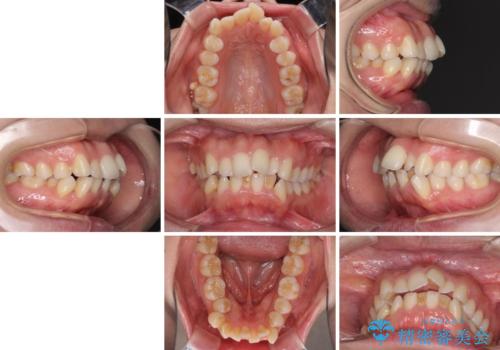

- 前歯のデコボコと口元の突出感を気にして来院された患者様です。

上下左右第一小臼歯4本を抜歯し、ワイヤー装置にて口元を引っ込めるよう矯正治療を行うこととしました。

叢生が強かったため、口元の突出感の改善には限界がありましたが、横側からも口元が引っ込んだ感じが分かるほど改善されました。